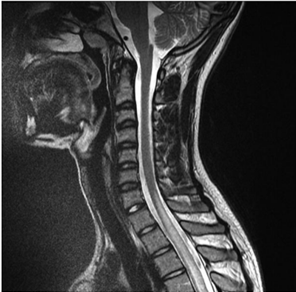

Paciente de 29 anos, sexo feminino, chega ao pronto atendimento apresentando fraqueza em membros inferiores, com três dias de evolução, que se associou à sensação de urgência urinária e constipação. Iniciou o quadro com alteração de sensibilidade nos membros inferiores e, no momento da admissão, não conseguia mais deambular. Na história pregressa, a paciente apresentava um quadro de artralgia e febre. No exame neurológico, entre outros achados, apresenta nível sensitivo em T2. Nos exames laboratoriais, observou-se pancitopenia, anti-DNA e anti-Sm positivos. A ressonância magnética da coluna cervical apresentou a seguinte imagem:

Em relação ao caso apresentado, é correto afirmar: